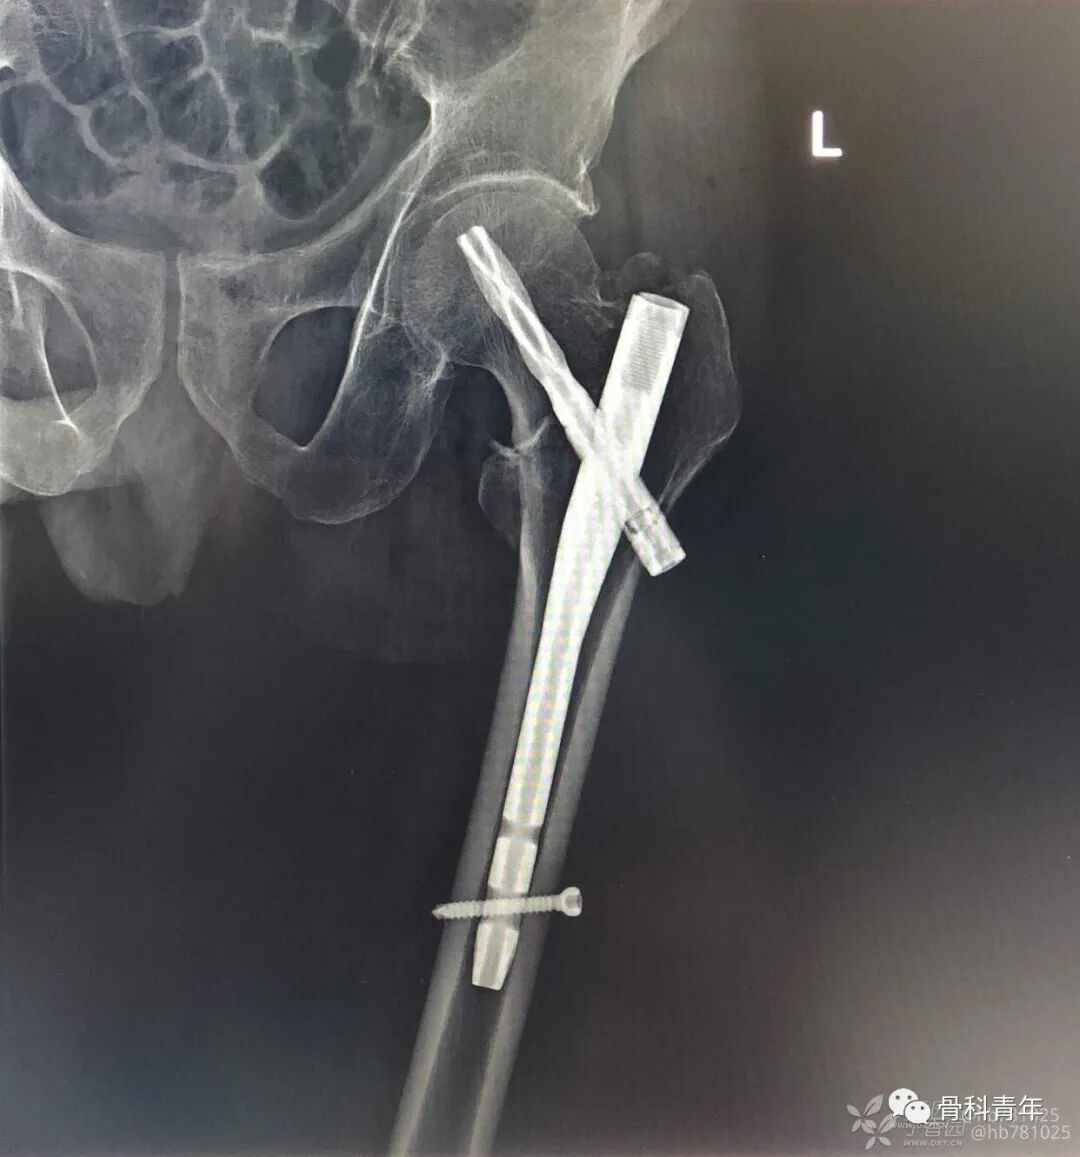

4.股骨骨折(髓内钉)